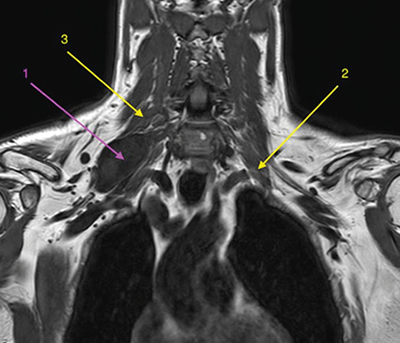

Figura 2